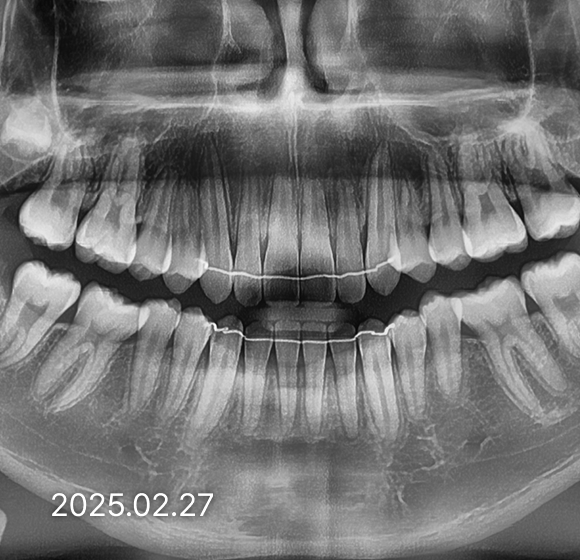

BEFORE / AFTER

전후 변화로 보는 치료사례

본 사진은 진심을담은치과교정과 치과의원에서

치료한 환자의 동일 인물 전·후 사진입니다.

개인의 구강 상태 및 관리 방법에 따라 통증 및 잇몸 염증,

턱관절 불편감 등의 부작용이 발생할 수 있습니다.

치료 전 치료 후

덧니, 삐뚤한 치열

돌출입

반대교합(비수술)

성장기 교정

과개교합

개방교합

치열공간, 벌어진 앞니

매복치아

악교정 수술 교정

결손치

부분교정

인비절라인